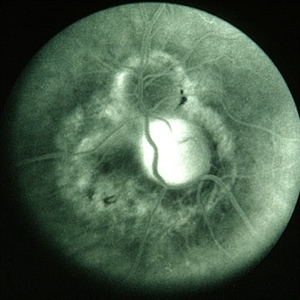

Toxocara granuloma of ON, late stage F/A. #3 Late hyperfluorescence in the granuloma due to staining.

Condition/keywords: ocular toxoplasmosis, toxocara granuloma, toxocariasis